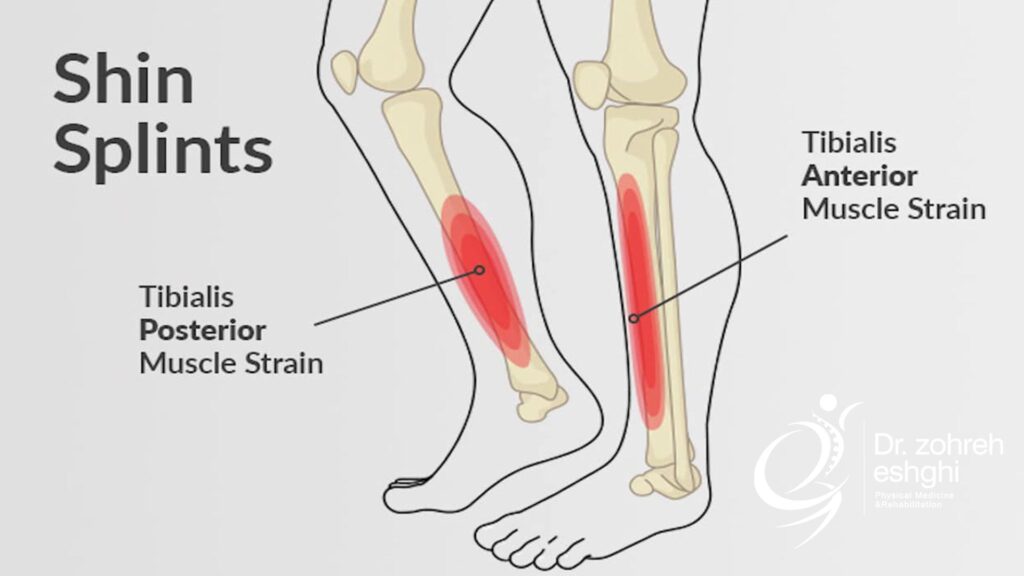

لخته خونی

گاهی اوقات، ترومبوز وریدی عمقی (DVT) علت درد ساق پا است. سیگار کشیدن، نداشتن فعالیت بدنی برای مدت طولانی یا مصرف برخی داروها، دلایل اصلی ایجاد ترومبوز ورید عمقی هستند.

در صورت عدم درمان، لخته خونی در وریدی عمقی، اغلب جدا شده و پس از ورود به جریان خون به رگ های ریه یا حتی قلب می رسد. این یک عارضه جدی به نام آمبولی ریه است.